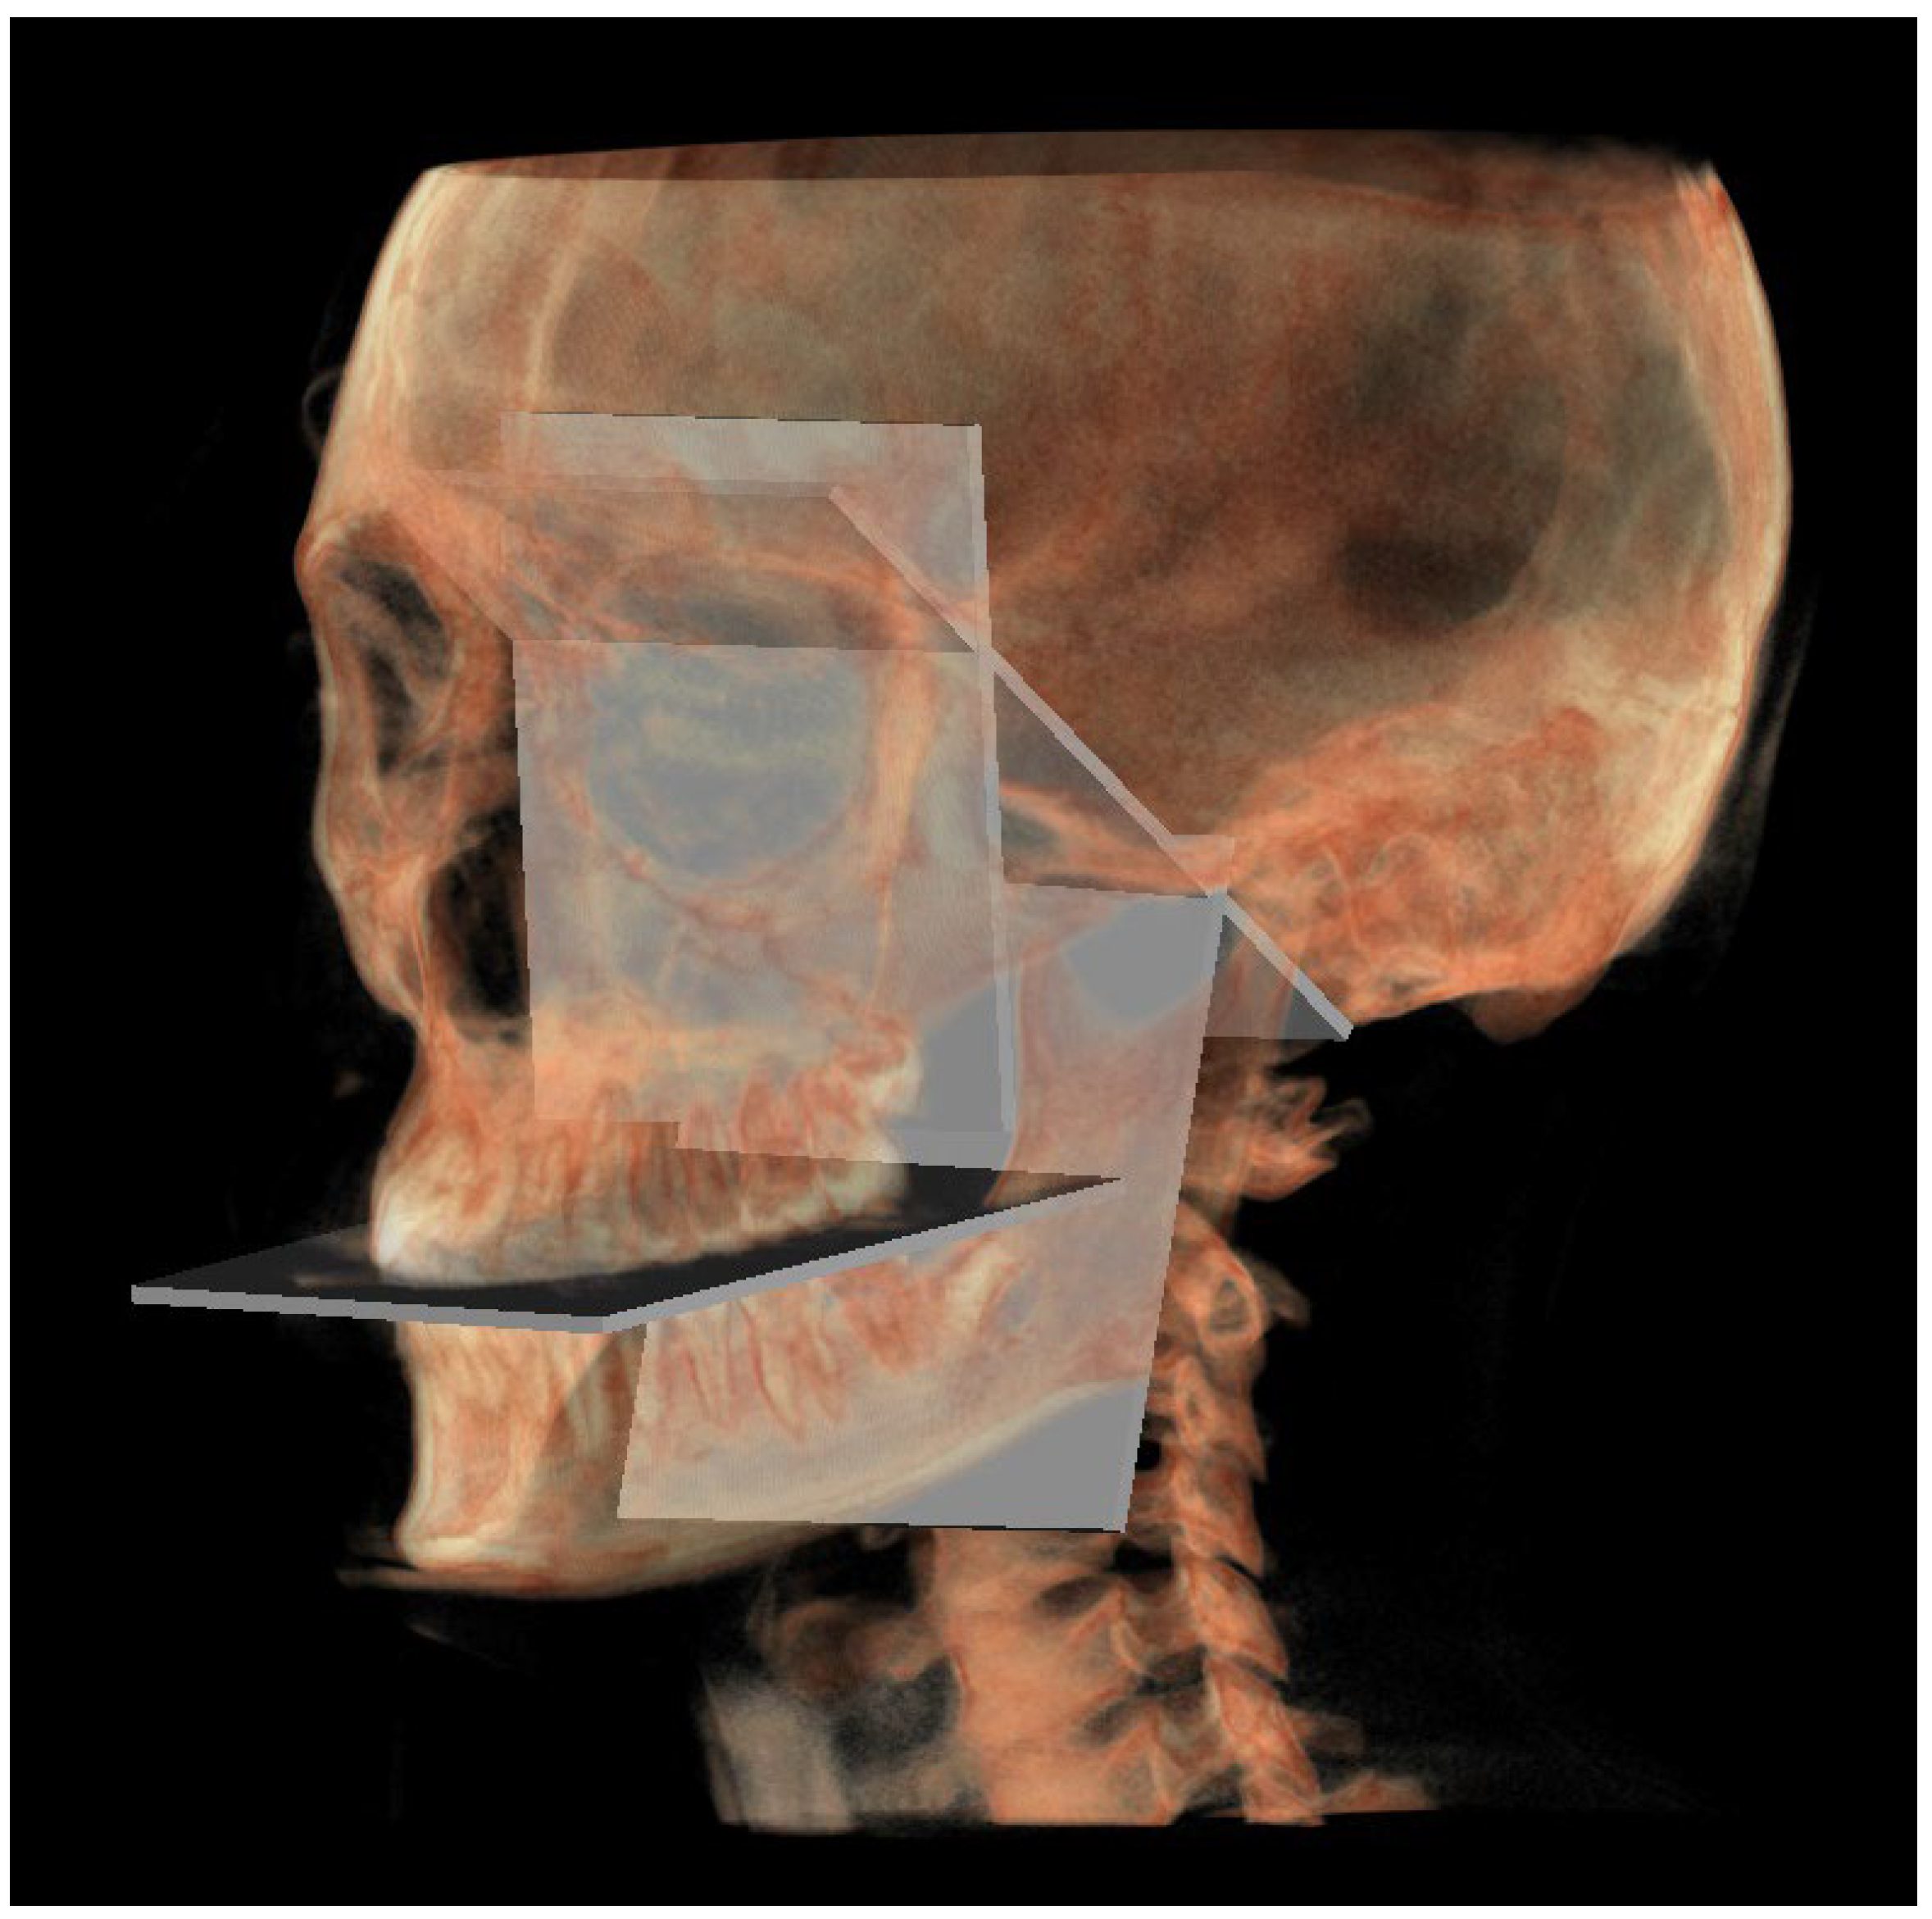

A representation of all 3D individual track planes (Figure 7).

Figure 7. All the planes of the 3D individual track.